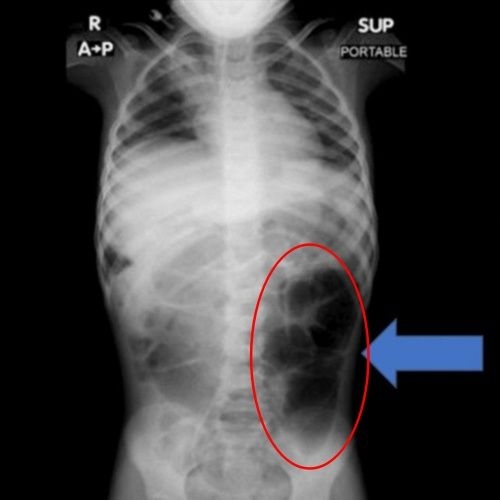

검사 결과 A양의 위 내부에서는 비정상적으로 큰 이물질이 발견됐고, 의료진은 즉각 수술을 결정했다. 제거된 이물질은 다량의 머리카락이 엉켜 형성된 덩어리로, 위에만 머무르지 않고 소장의 일부까지 길게 이어진 상태였던 것으로 확인됐다.

이 같은 질환은 '라푼젤 증후군'으로 불린다. 머리카락을 뽑아 먹는 습관인 발모식증이나 모발섭식증으로 인해 위 속에 머리카락 덩어리가 형성되고, 이것이 소장까지 길게 이어지는 매우 희귀한 질환이다. 동화 속 라푼젤처럼 머리카락이 길게 늘어진 모습과 닮았다는 점에서 이름이 붙여졌다.

라푼젤 증후군은 주로 청소년과 젊은 여성에게서 나타나며, 불안·강박·스트레스 등 심리적 요인과 동반되는 경우가 많다. 주요 증상으로는 복통과 복부 팽만, 구토, 소화불량, 체중 감소, 식욕 부진 등이 있으며, 심한 경우 장 폐색이나 출혈, 장 천공으로 이어질 수 있다.